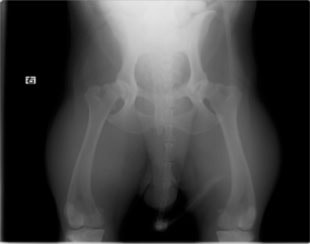

ボール遊びの後の後肢の跛行を主訴に来院されました。院内ではモンローウォーク(腰を振って歩く歩様)が認められました。レントゲン検査において、左右股関節の形成不全および比較的重度の関節炎所見を認めました。左右ともに長期に及ぶ骨関節炎の進行により、寛骨臼に重度の骨変形・骨硬化が認められました。このような症例においては、THRのカップの定着が悪くTHRの手術の成功率が下がるため、機能回復の面では劣りますが、症状がより重く、筋肉の萎縮の認められた右後肢の大腿骨頭・骨頚切除術を実施しました。関節面に関節軟骨の欠損、骨増殖体を認めました。今後は、リハビリテーションを行い、患肢の機能回復に努め、反対側の大腿骨頭・骨頚切除術を検討していく予定です。

術前レントゲン

術後レントゲン